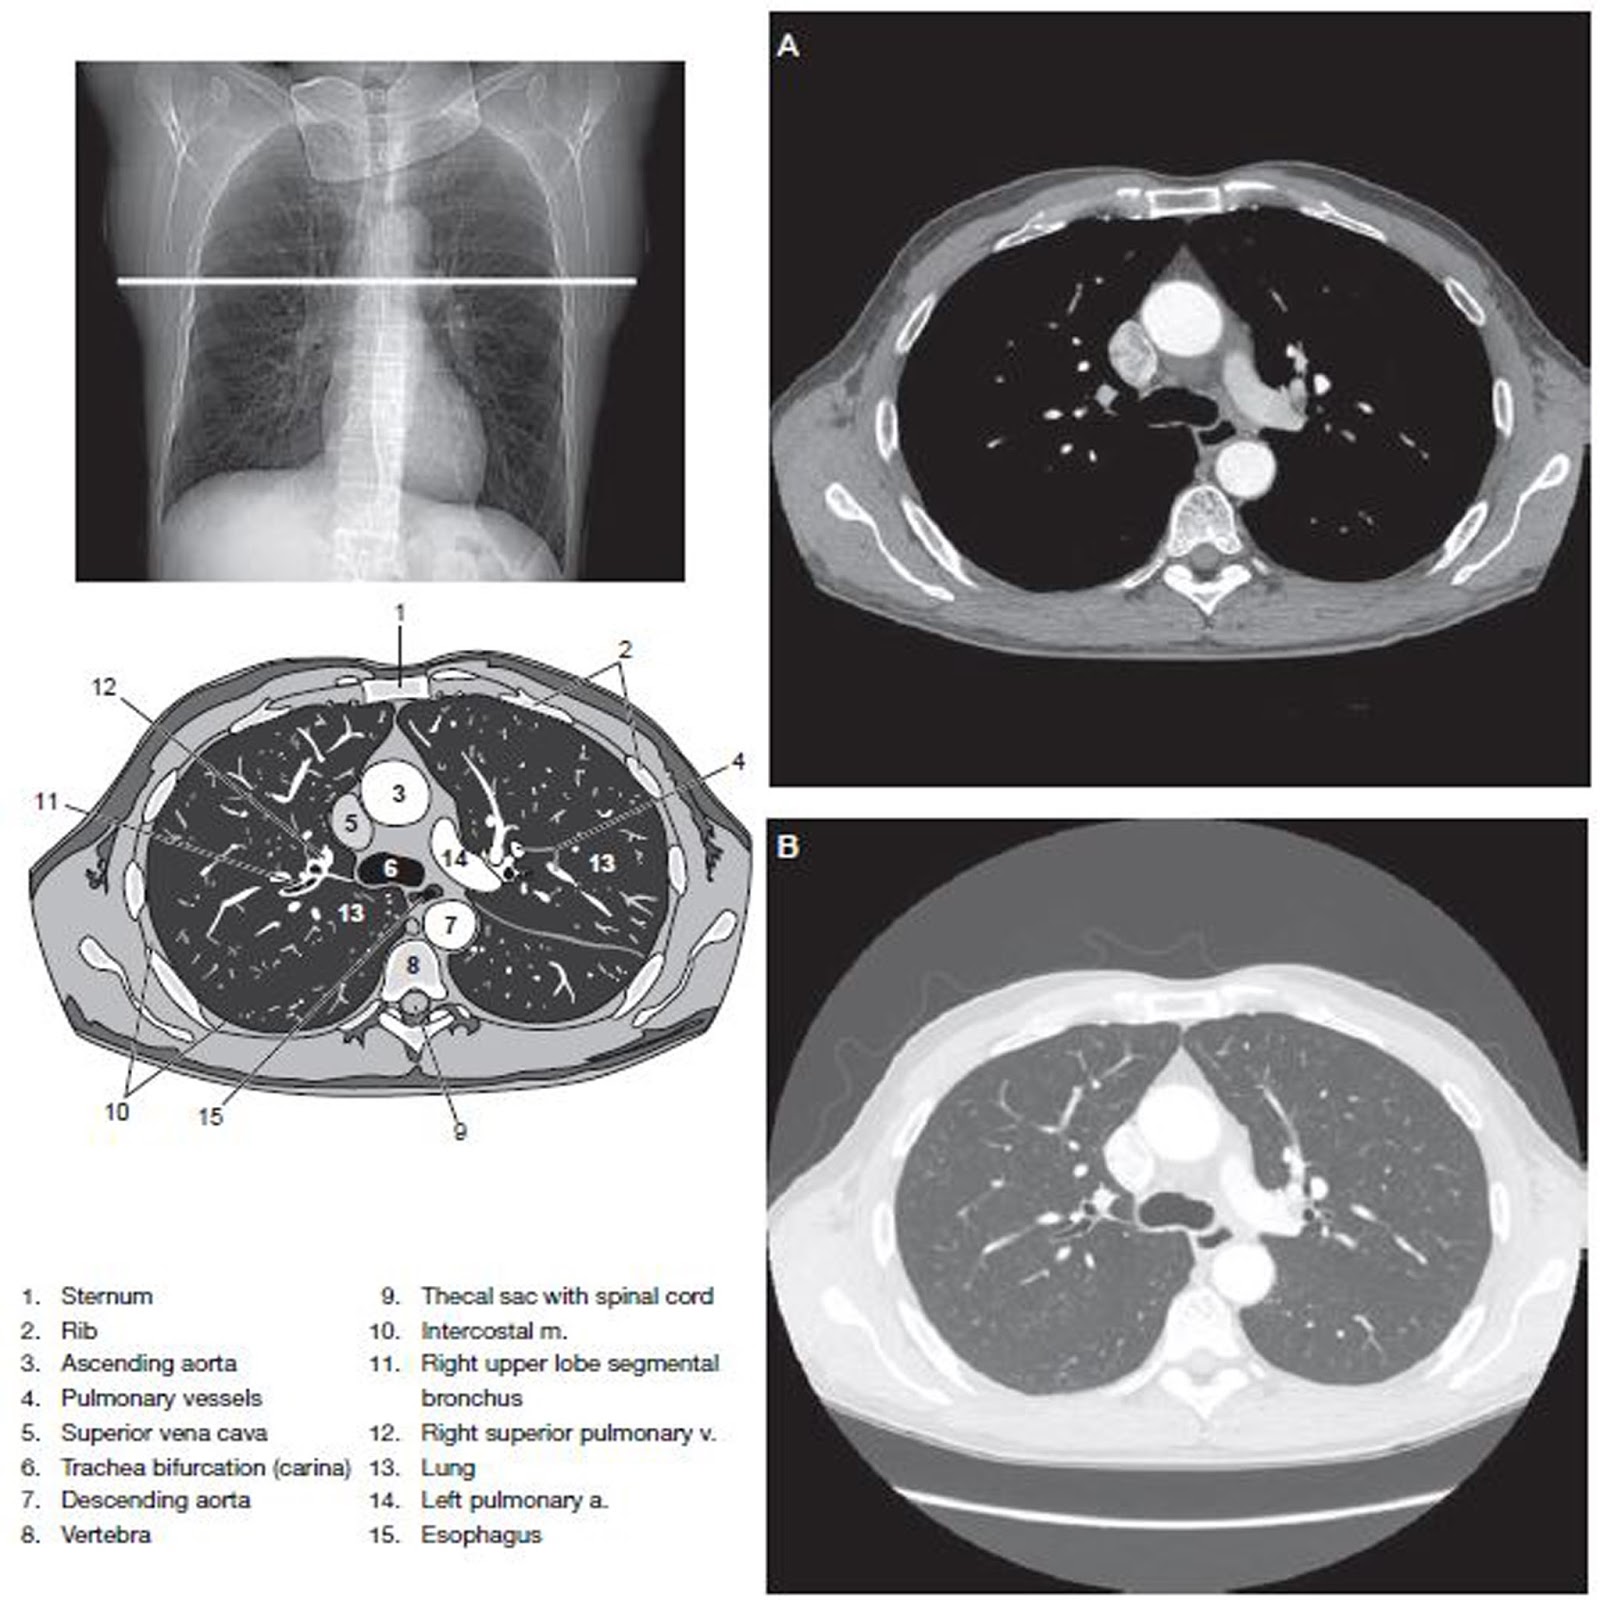

Recognizing Xiphoid Process cancer symptoms is crucial for early diagnosis. Learn about common warning signs, including persistent chest pain, unusual lumps, or tenderness near the sternum. Understanding these clinical indicators and potential underlying malignancies helps you identify when to seek professional medical advice. Stay informed about diagnostic procedures and health concerns related to this rare area of the body.

Read full article: Xiphoid Process Cancer Symptoms